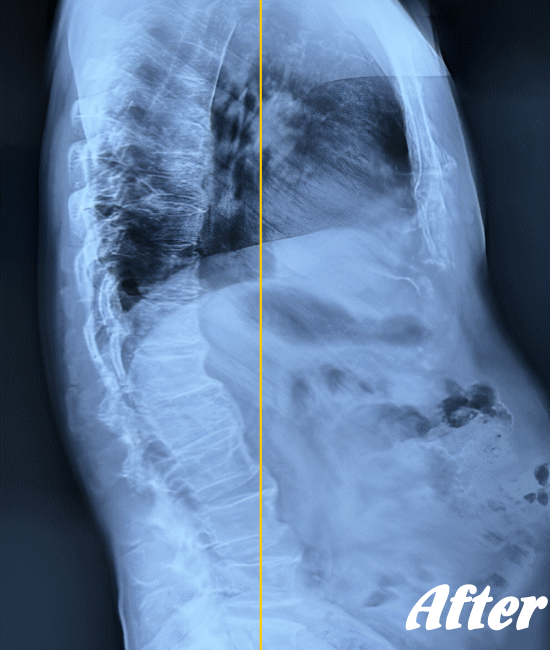

身体に無理をかけず骨や関節の位置を解剖学的に正しい位置へ調整することで、痛みを取り除いていきます。慢性化した痛みも改善します。

多くの場合、頸椎(首の骨)、肩甲骨、背中の胸椎(背骨)、肋骨、そして骨盤(仙腸関節)を調整すれば、痛みは早い段階でなくなり、健康な状態に回復します。